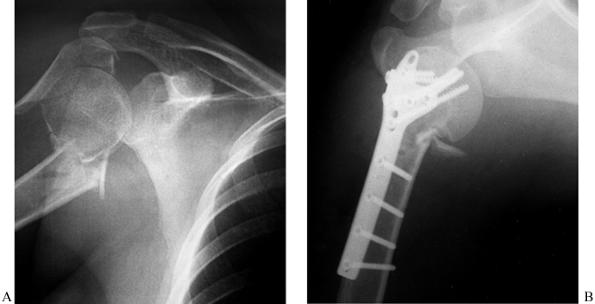

If the glenoid neck fracture is

associated with a second injury such as a clavicle fracture or

acromioclavicular joint disruption, then address the injury that is

more accessible first. Usually that means open reduction and plate

fixation of the clavicle (Fig. 15.9). If the

fixation is solid and reduces the associated glenoid neck fracture

within the criteria listed above, then no further internal fixation is

required. If the glenoid neck remains displaced beyond acceptable

criteria, however, then we openly reduce and fix that fracture also.

Figure 15.9. A: Displaced glenoid neck fracture associated with a clavicle fracture. B: Indirect reduction of glenoid neck fracture after open reduction and internal fixation of the clavicle. -